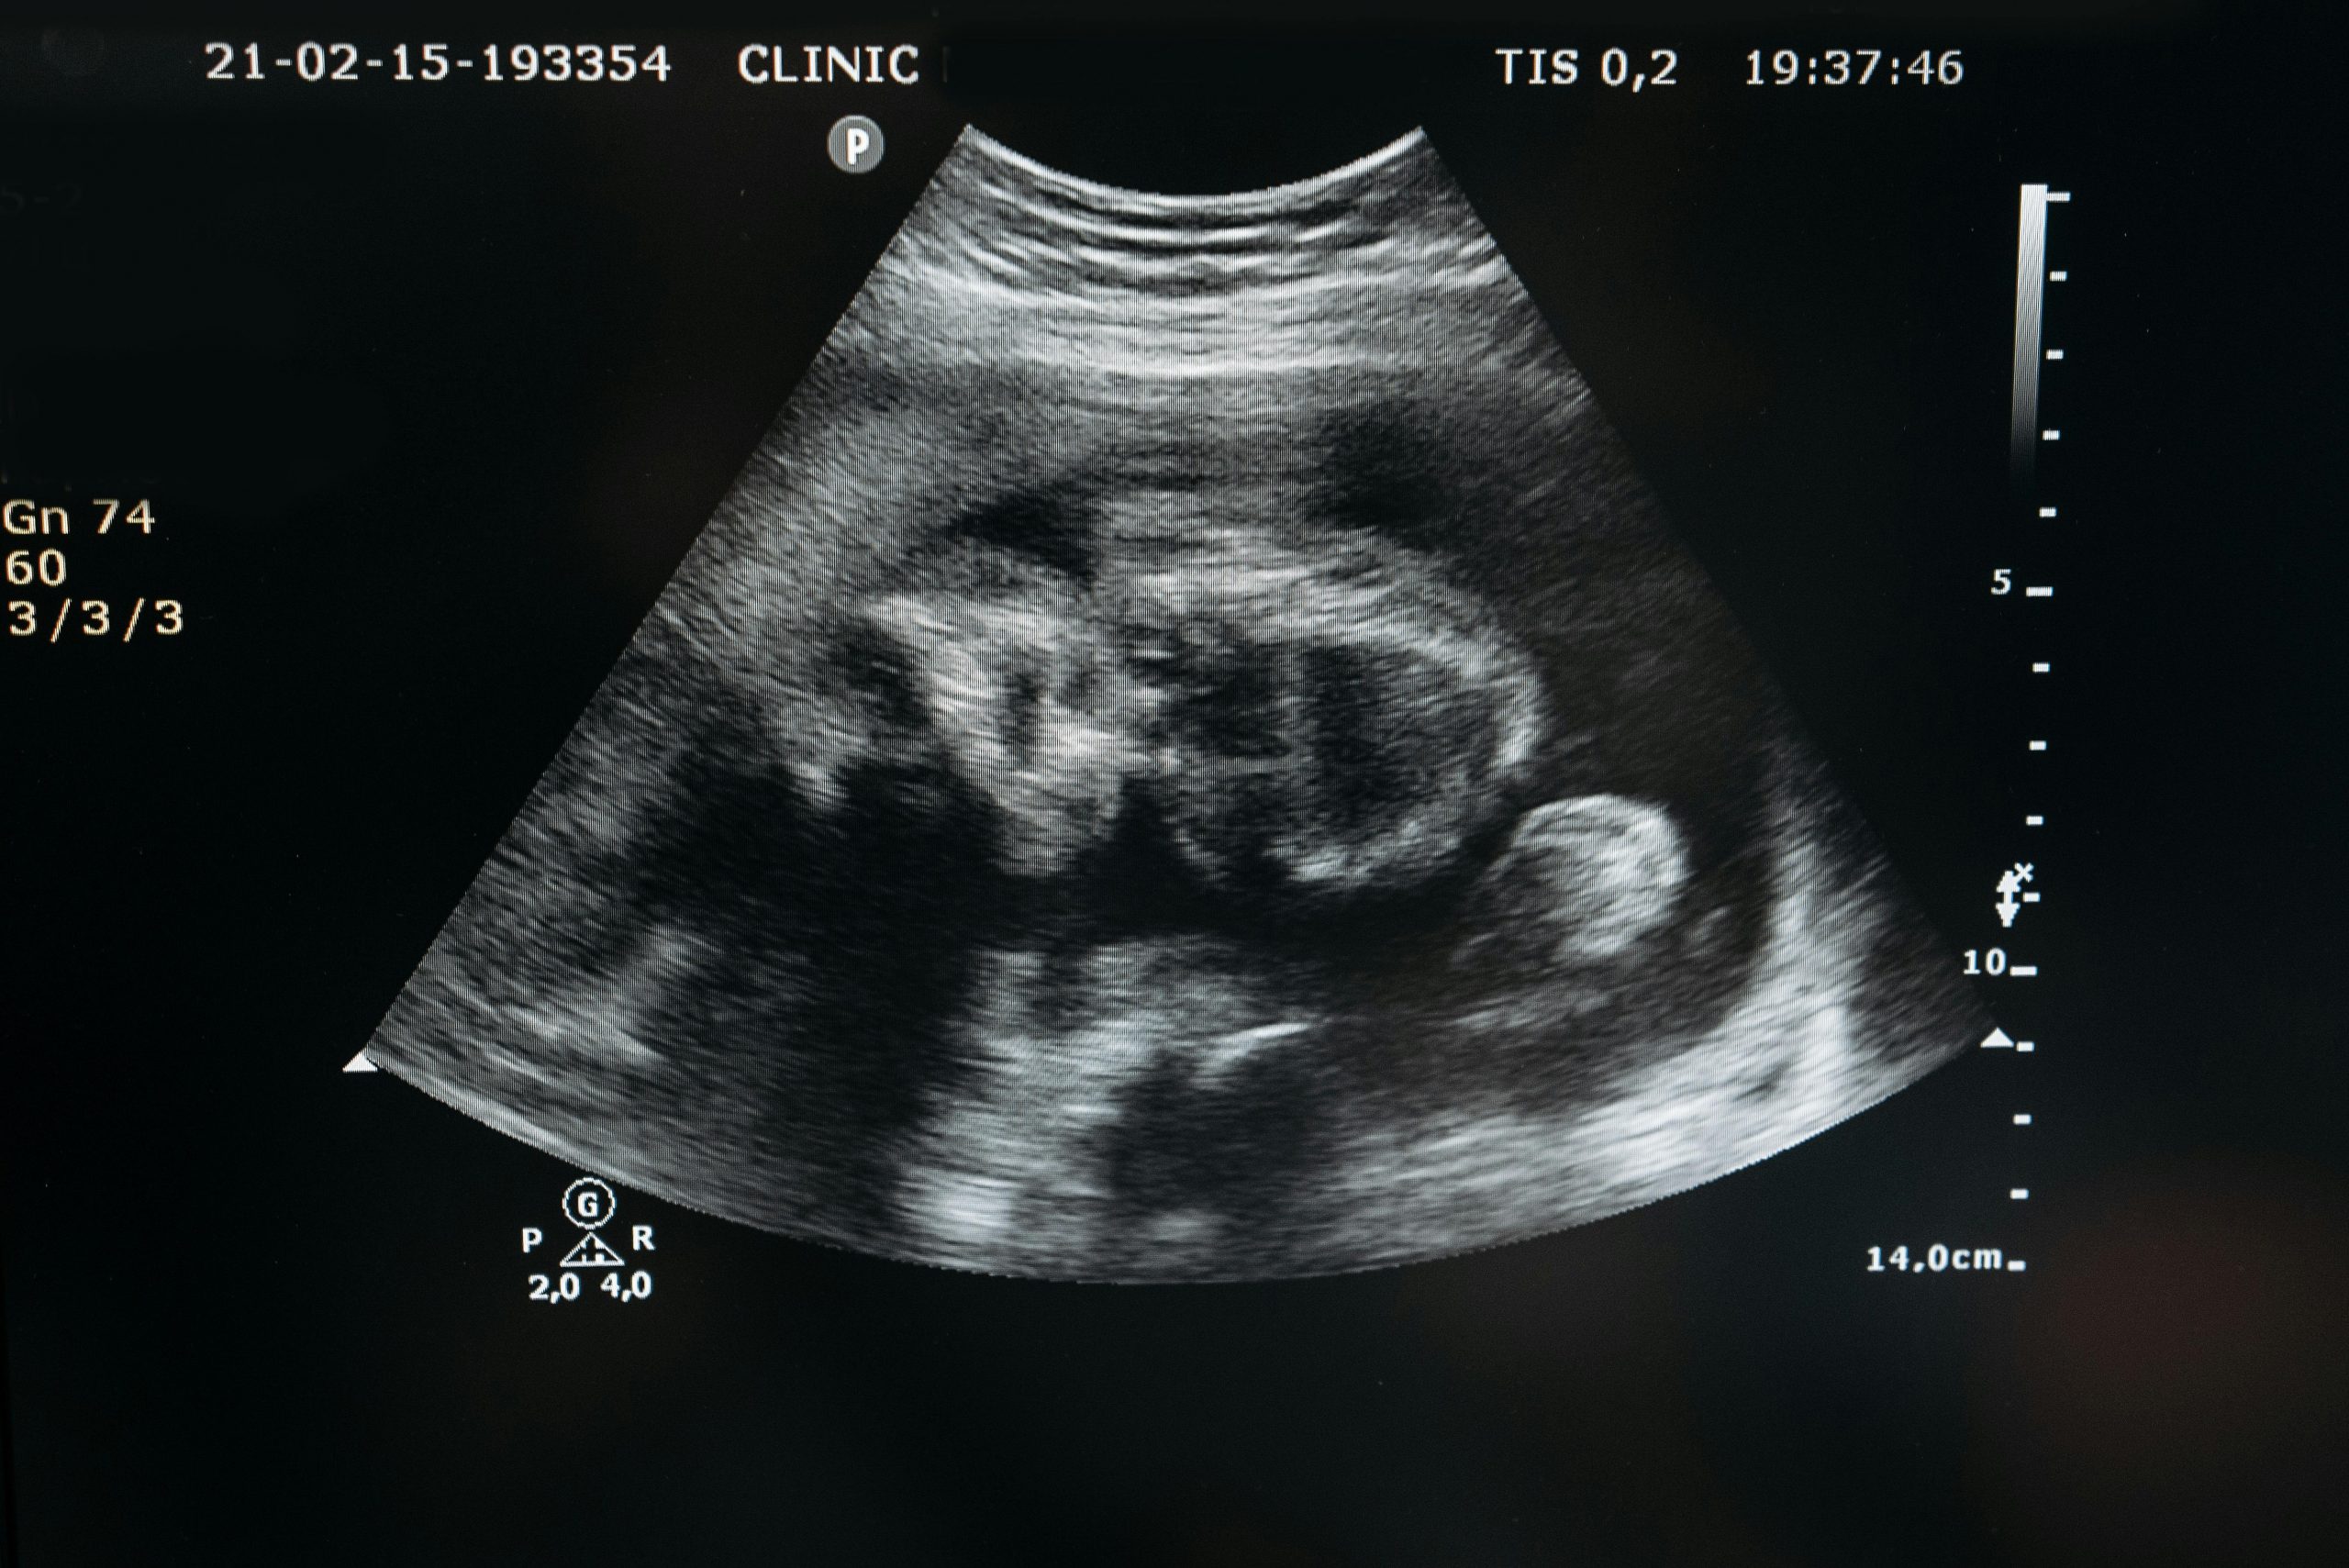

Ecografías

Pruebas diagnósticas obstétricas